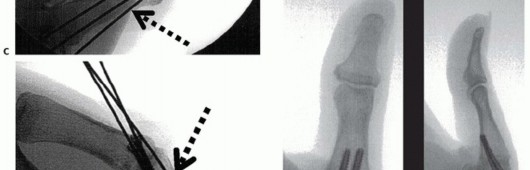

TECH FIG 2 • (continued) E. A Kirschner wire is drilled across the MP joint to keep it flexed 30 degrees, protecting the repaired volar structures during initial healing. VariationsSchuurman and Bos12: Place sutures through the proximal edge of the volar plate and pass them through the metacarpal via the Keith needles. Reinforce the construct with nonabsorbable sutures to local tissue where possible.Eaton and Floyd1: Place sutures in the proximal corner of the volar plate and pass them subperiosteally from volar to dorsal around the metacarpal and secure them to advance the volar plate snugly into the prepared retrocondylar fossa.Pin the MP joint in about 30 degrees of flexion using a Kirschner wire (TECH FIG 2E). Close the wound in routine fashion and apply dressings and a thumb spica splint.Remove the sutures at 10 to 14 days as usual and apply a thumb spica cast.Remove the Kirschner wire and cast at 4 weeks and begin active flexion exercises using a removable protective splint for an additional 2 weeks.